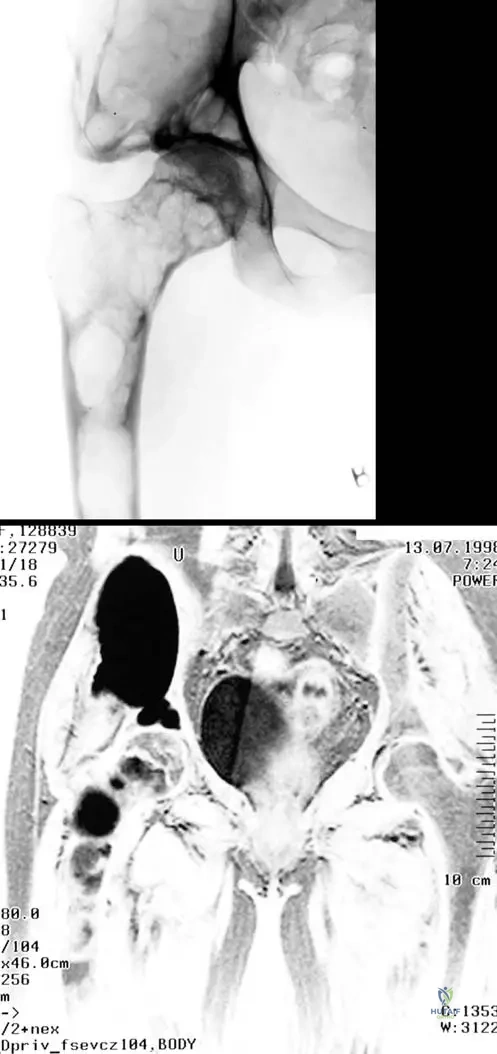

A 16-year-old female with polyostotic fibrous dysplasia affecting her femur and pelvic bone undergoes an MRI for further evaluation of a painful lesion. What general appearance would be expected on MRI, consistent with the radiographic findings?

View Answer & Explanation

Correct Answer: C

Rationale: The text states that "The lesions are usually benign-appearing, presenting a bubbly lytic or mixed lytic and sclerotic lesions with a narrow zone of transition and a sclerotic margin as seen in this patient with polyostotic disease affecting both the femur and pelvic bone as presented on the radiograph (a) and MR imaging (b)." This description directly applies to the expected appearance on MRI as well, reflecting the mixed fibrous and osseous components. Aggressive periosteal reaction would suggest a malignant process.